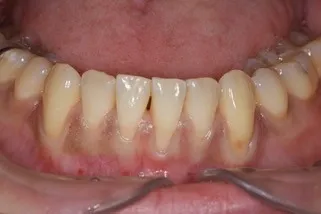

歯茎が下がり歯が長く見えたり、冷たいものがしみたりするお悩みに対し、歯肉移植治療を行っています。歯周病や年齢に伴う変化、過度な歯磨きなどにより下がった歯茎に、ご自身の上顎から採取した組織を移植する方法です。露出した歯の根元を覆うことで、見た目の改善や知覚過敏の改善を目指します。マイクロスコープを用いた精密な処置で、身体へのご負担を少なくするよう努めています。

歯肉退縮とは、歯茎が痩せて下がってくる現象を指します。

歯肉退縮が進むと、もともとは歯茎によって隠れていた歯の根元の部分が見えるようになり、見た目が悪くなり、食べ物が詰まる、汚れが溜まるといった不便も生じます。

- 歯茎の痩せる・下がる

- 歯が長くなったように見える

- 歯の根が露出することによる知覚過敏

- 露出した歯の根の虫歯